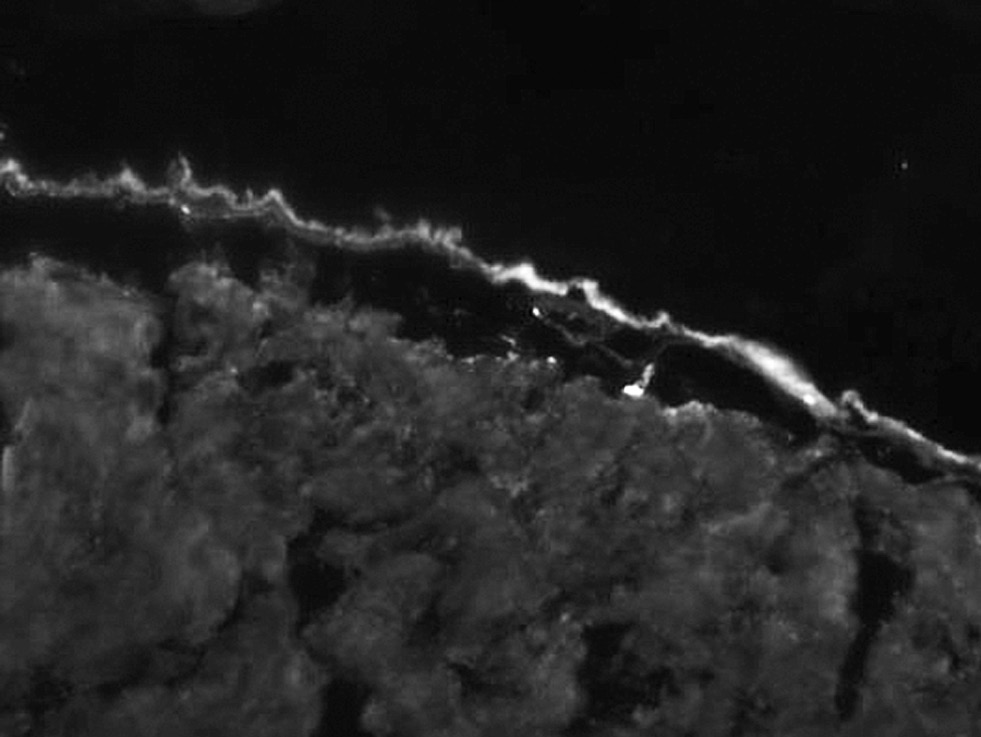

Результаты физикального, лабораторного и инструментального исследования. При постановке реакции иммунофлюоресценции определяется линейное отложение IgG, IgM вдоль базальной мембраны. В реакциях с антителами IgA свечения нет (рис. 2). При гистохимическом исследовании обнаружены субэпидермальные пузыри, состоящие из малодифференцированных фибробластов; в верхней части дермы и утолщённых стенках капилляров имеются отложения гиалина (рис. 3). В стенках сосудов выявлены ШИК*-положительные диастазорезистентные вещества (рис. 4).

Рис. 2. Линейное отложение IgG и IgM вдоль базальной мембраны; IgA ― свечения нет. ×50. / Fig. 2. Linear deposition of IgG, IgM along the basement membrane; IgA ― no luminescence. ×50.